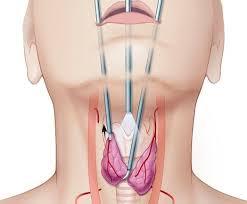

ENT Clinic in Rahatani,Kalewadi,Pimple Saudagar,PCMCENT Surgeon,ENT Doctor in Rahatani,Kalewadi,Pimple Saudagar,PCMCENT Specialist,ENT Surgeon in Rahatani,Kalewadi,Pimple Saudagar,PCMCEar Cleaning Clinic in Rahatani,Kalewadi,Pimple Saudagar,PCMCEar Lobe Repair Clinic in Rahatani,Kalewadi,Pimple Saudagar,PCMCEar Nose Piercing Clinic in Rahatani,Kalewadi,Pimple Saudagar,PCMCKeloid Excision Clinic in Rahatani,Kalewadi,Pimple Saudagar,PCMCHearing Evaluation Clinic in Rahatani,Kalewadi,Pimple Saudagar,PCMCHearing Aid Clinic in Rahatani,Kalewadi,Pimple Saudagar,PCMCTympanoplasty Clinic in Rahatani,Kalewadi,Pimple Saudagar,PCMCHeadache and Vertigo Evaluation Clinic in Rahatani,Kalewadi,Pimple Saudagar,PCMCNasal And Laryngeal Endoscopy Clinic in Rahatani,Kalewadi,Pimple Saudagar,PCMCAllergy Test-Skin Prick Test Clinic in Rahatani,Kalewadi,Pimple Saudagar,PCMCSeptoplasty Clinic in Rahatani,Kalewadi,Pimple Saudagar,PCMCSinusitis Treatment Clinic in Rahatani,Kalewadi,Pimple Saudagar,PCMCEndoscopic Sinus Surgery Clinic in Rahatani,Kalewadi,Pimple Saudagar,PCMCEndoscopic DCR Clinic in Pimple Saudagar,PCMCMucormycosis Diagnosis And Treatment Clinic in Rahatani,Kalewadi,Pimple Saudagar,PCMCTonsillectomy Treatment Clinic in Rahatani,Kalewadi,Pimple Saudagar,PCMCEvaluation of Voice Change And Difficulty in Swallowing Clinic in Pimple Saudagar,PCMCAdenoid Surgery Clinic in Rahatani,Kalewadi,Pimple Saudagar,PCMCEvaluation of Neck Swelling (Thyroid) Clinic in Rahatani,Kalewadi,Pimple Saudagar,PCMCThyroid Surgery Treatment in Rahatani,Kalewadi,Pimple Saudagar,PCMCDiagnosis of Head And Neck Cancers Treatment in Rahatani,Kalewadi,Pimple Saudagar,PCMC